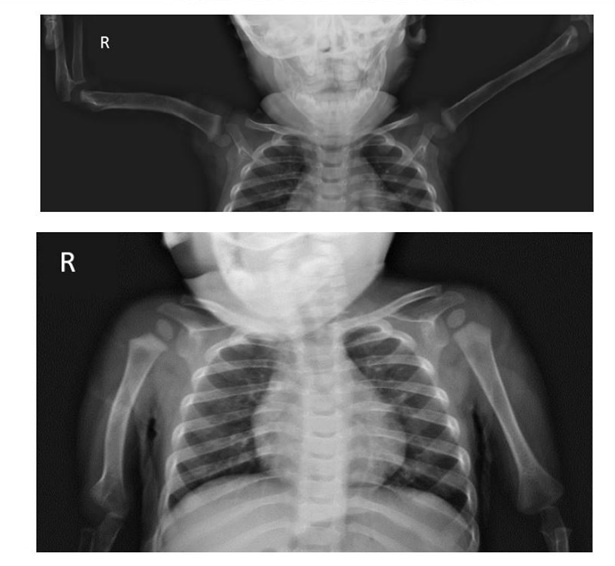

Follow-up radiographs at 13 months of age showed anatomic reduction of the fracture, as well as mild shortening of the right humerus and anterior bowing of the diaphysis. The ossification center of the humerus was symmetrical to the contralateral side, with no evidence of avascular necrosis (Figures 4 and 5). Physical examination revealed symmetrical range of motion in both arms.